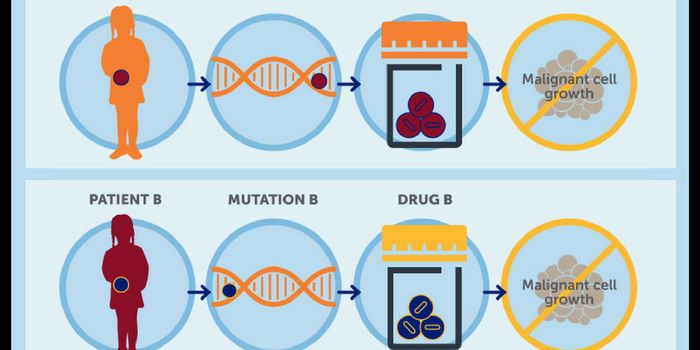

JUN 05, 2018CancerSo often the phrases "Precision Medicine" and "Personalized Medicine" are used interchangeably. Are they really synonym ...

FEB 12, 2019CancerCancer is on everybody's mind these days. Many pharmaceutical companies are devoted solely to finding new cancer tre ...

AUG 11, 2016CancerIn 2014 the most common cancer diagnosis was breast cancer, followed by prostate, lung, colon, skin, and brain cancer. B ...

APR 06, 2015CancerNorthwestern Medicine scientists have identified a small RNA molecule called miR-182 that can suppress cancer-causing ge ...